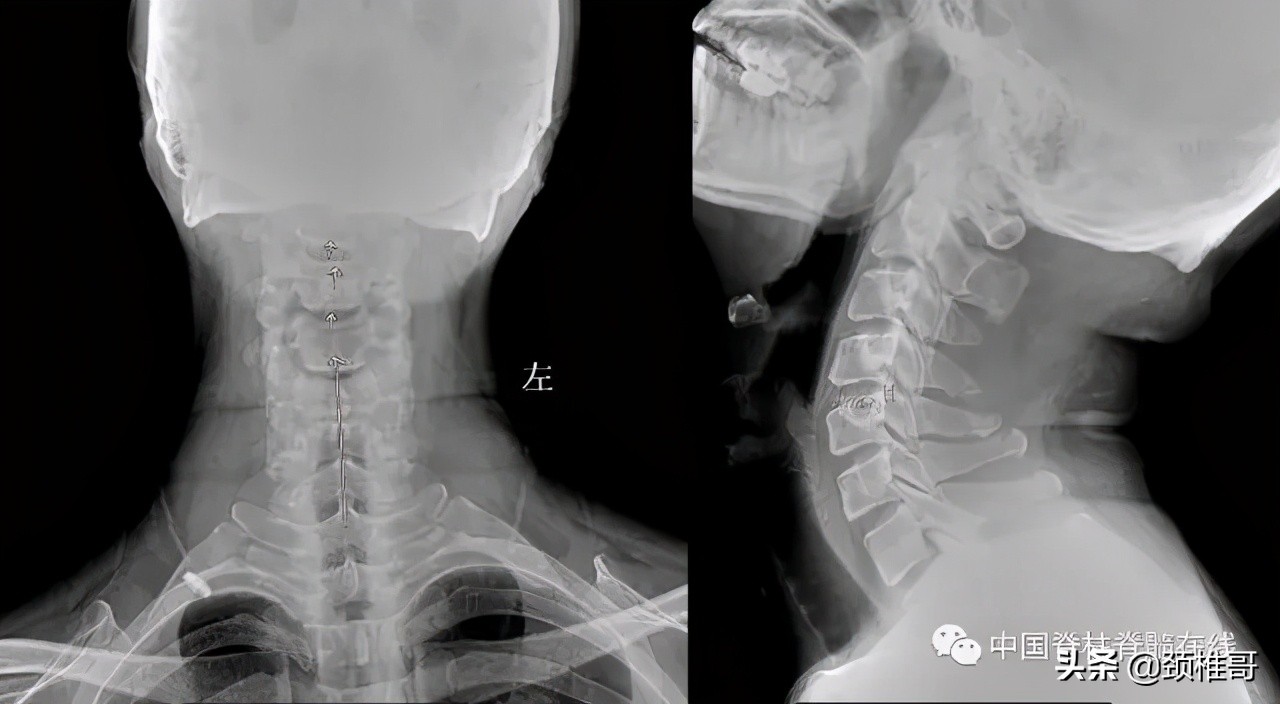

再看看这个病人,头晕2年,转头、低头时头晕加重,他的核磁共振显示椎间盘退变,水分减少了,但是没有明显的椎间盘突出,充其量算是膨出,但是我们看看他的x线片:颈椎3-5棘突序列不整齐,侧位显示颈椎5/6之间夹角增大,过伸位片显示,颈椎4-7各个节段夹角都超过了11°。过屈侧位片显示5、6、7三个节段出现了双边征,是椎体发生了旋转不稳的结果。这个病例的主要问题在于椎间盘吗?不对,在于肌肉和韧带对于颈椎4-7各个节段之间的稳定控制能力的减退。

正位:颈椎序列欠佳 侧位:颈椎4-7夹角增大

对节段颈椎成角过大、双边征

MRI显示颈椎多节段椎间盘退变膨出